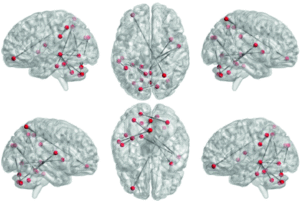

Morphometric and Functional Brain Connectivity Differentiates Chess Masters From Amateur Players

Authors: RaviPrakash, H., Anwar, S. M., Biassou, N. M., & Bagci, U.

Frontiers in Neuroscience - 2021

Publication Year: 2021